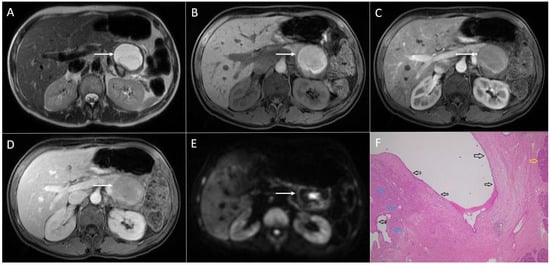

2. Typical Imaging Presentation of Solid Pseudopapillary Neoplasms